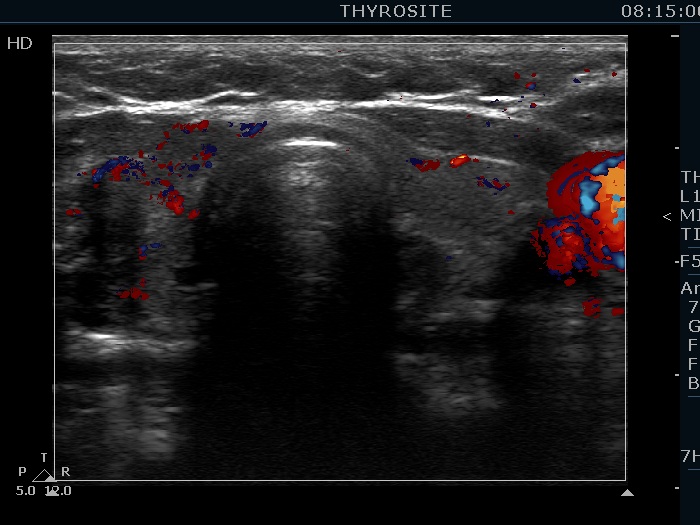

Ethanol sclerotherapy: toxic nodules - Case 2

Two years after repeated therapy (ultrasonographic picture 6)

Left lobe, longitudinal scan, color Doppler mode.